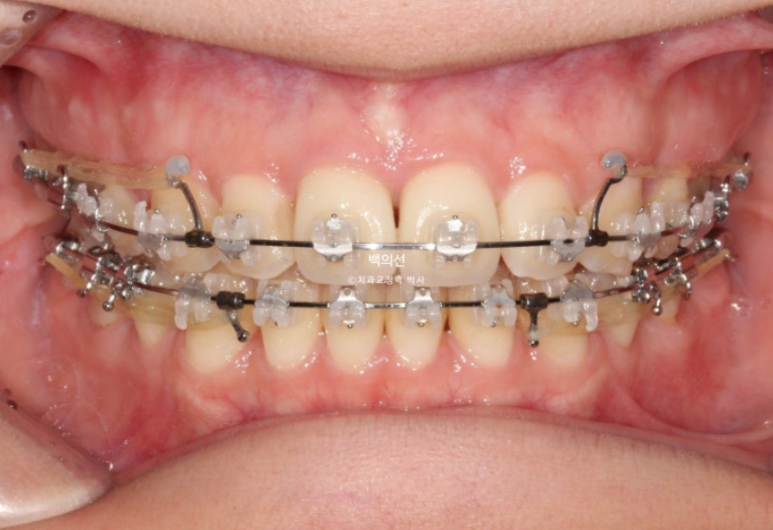

지난 2월 타병원에서 이미 2년 10개월째 클리피씨 발치교정을 진행하던 환자분이 오셨습니다.

교정치료 도중 머리부위에 MRI를 찍을 일이 많이 생겨서 인비절라인으로 치료를 마무리하고 싶어 오셨습니다.

치료기간이 이미 2년 10개월이 된만큼 교정치료 마무리 단계입니다.

인비절라인 장치제작을 위해 클리피씨 장치를 제거한 직후입니다.